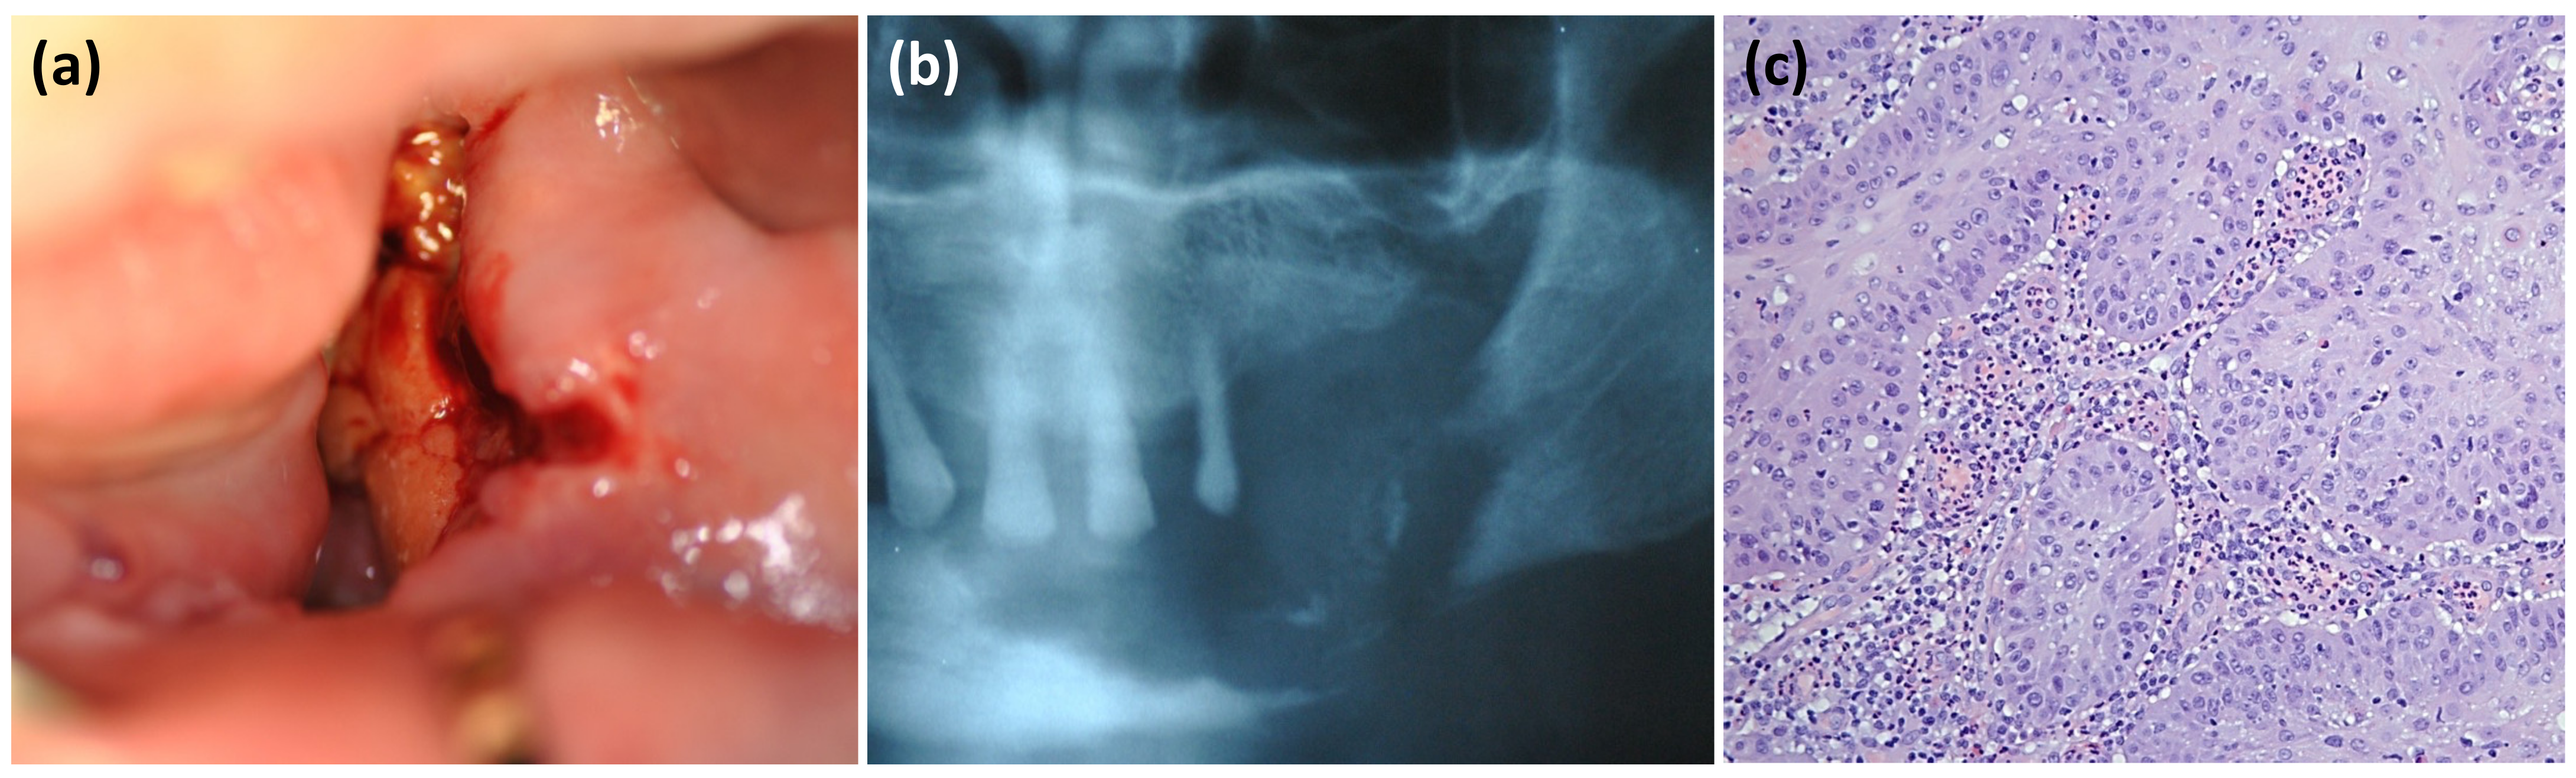

Oral Squamous Cell Carcinoma Mimicking Medication-Related Osteonecrosis of the Jaws (MRONJ): A Case Series

2. Case Presentation